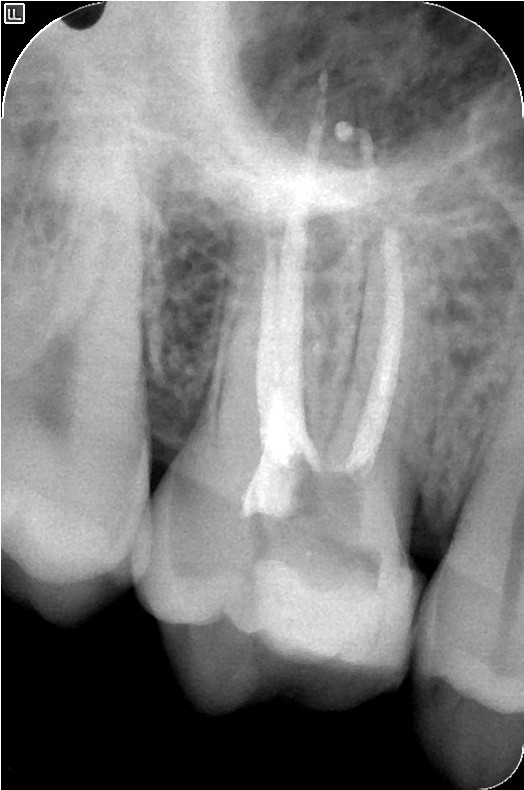

Below we see two images: the first is of a traditional radiograph with some pathology visible around the roots of an upper molar, and the second is an image showing 2D slices of pathology visible around the entire tooth and sinus.

The actual 3-D image can be manipulated to show any combination of slices so one can "move through the tooth" to check for potential issues.